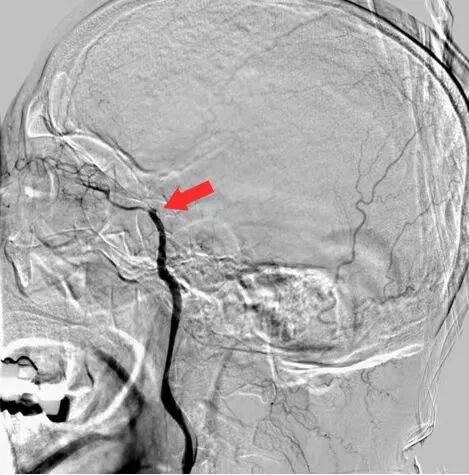

术前DSA

什么叫桡鞘【例久弥新】寻道于桡——瑞康通5.5F Introsky X导管鞘经桡取栓一例_https://www.jmylbn.com_新闻资讯_第8张

什么叫桡鞘【例久弥新】寻道于桡——瑞康通5.5F Introsky X导管鞘经桡取栓一例_https://www.jmylbn.com_新闻资讯_第9张

什么叫桡鞘【例久弥新】寻道于桡——瑞康通5.5F Introsky X导管鞘经桡取栓一例_https://www.jmylbn.com_新闻资讯_第10张

什么叫桡鞘【例久弥新】寻道于桡——瑞康通5.5F Introsky X导管鞘经桡取栓一例_https://www.jmylbn.com_新闻资讯_第11张

什么叫桡鞘【例久弥新】寻道于桡——瑞康通5.5F Introsky X导管鞘经桡取栓一例_https://www.jmylbn.com_新闻资讯_第12张